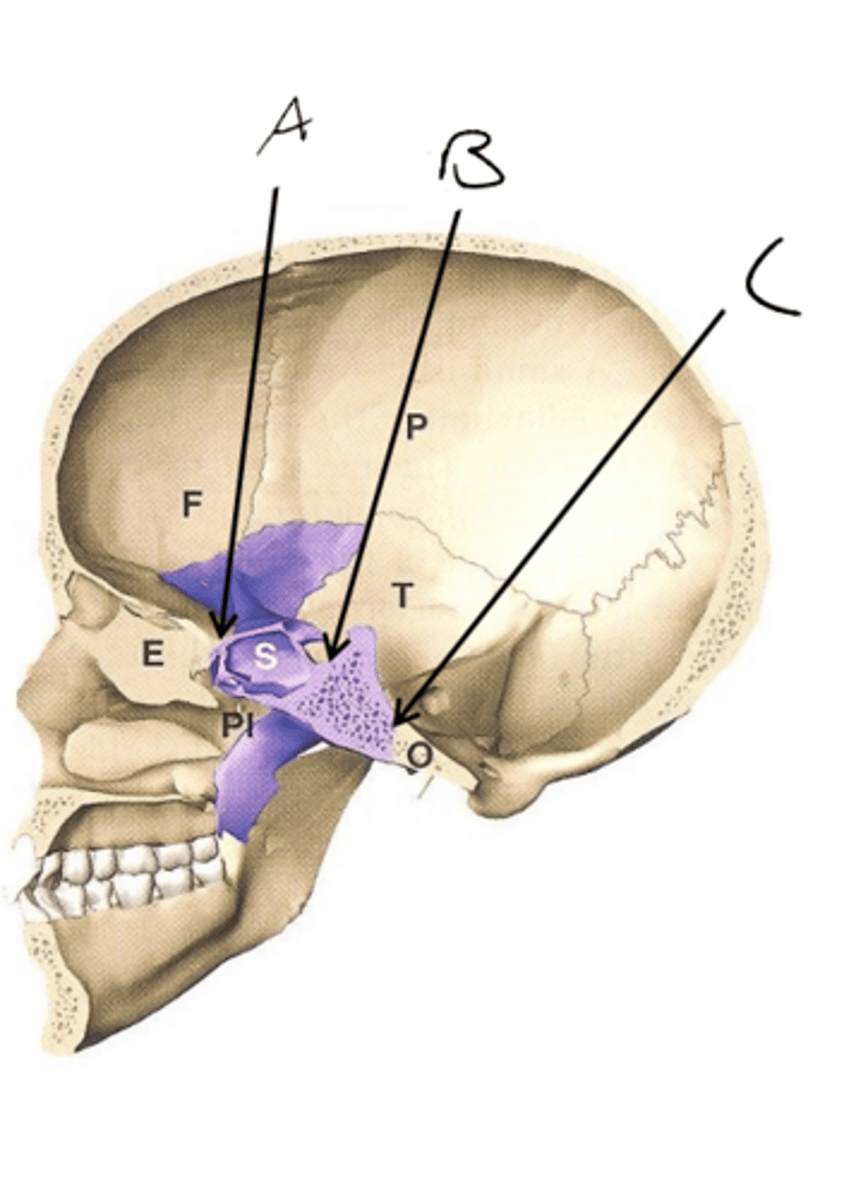

Neurocranium

A. Cranial base

B. Cranial vault

Viscerocranium

A. Orbital region

B. Nasal region

C. Masticatory region

knowt flashcard image

A. Cranial vault

B. Cranial base